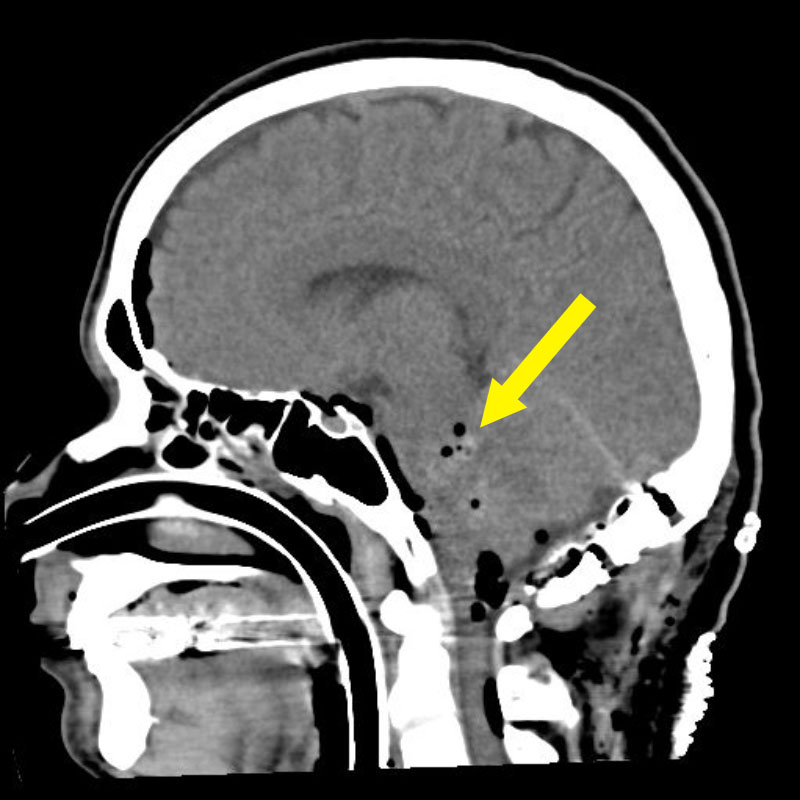

'19年5月

50代

富永

松田

右基底核視床

海綿状血管腫

多発出血性

青森県の病院

より紹介

No.No.28 手術前1

No.No.28 手術前2

No.No.28 手術後1

No.No.28 手術後2

CT/MRにより完全に摘出されたことが確認された